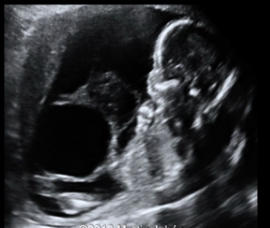

USA ectopic pregnancy

Complex adnexal mass located between ovary and UT

Fetal heart motion may be seen

Adnexal tubal ring (bagel or donut sign)

RING OF FIRE (increased vascularity surrounding decidual reaction)

Ectopic